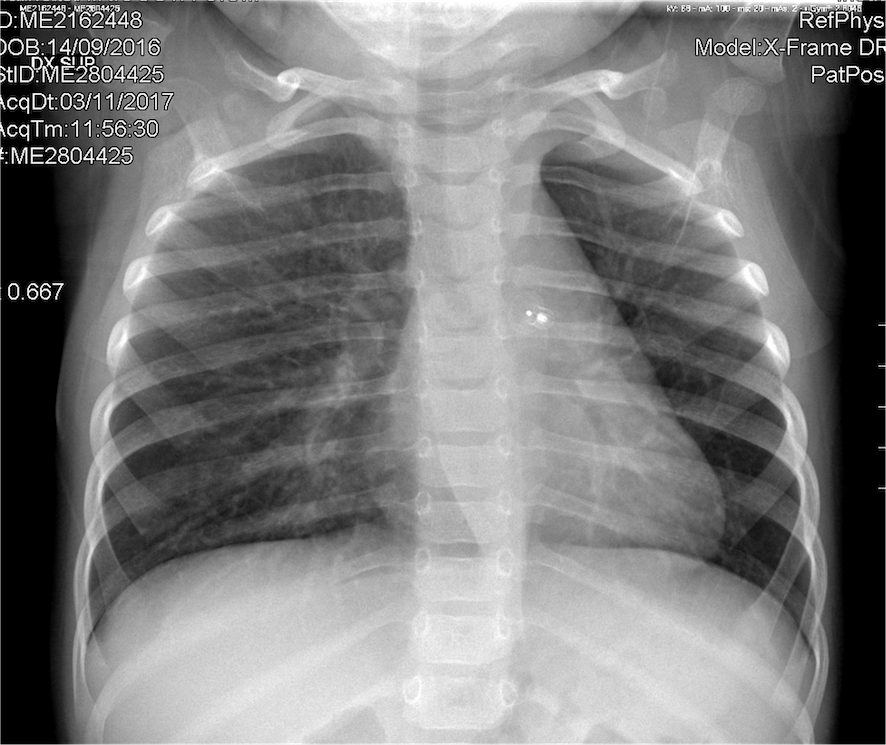

Dopo quest’ultima infezione, al controllo clinico, il curante ha riscontrato all’ascultazione toracica un murmure vescicolare costantemente ridotto alla base polmonare di sinistra, senza riferiti episodi di inalazione di corpi estranei. Così, a soli 13 mesi, il bambino giungeva alla nostra osservazione per eseguire la terza Rx torace, che mostrava ipodiafania del polmone sinistro, in assenza di addensamenti (Figura 1).